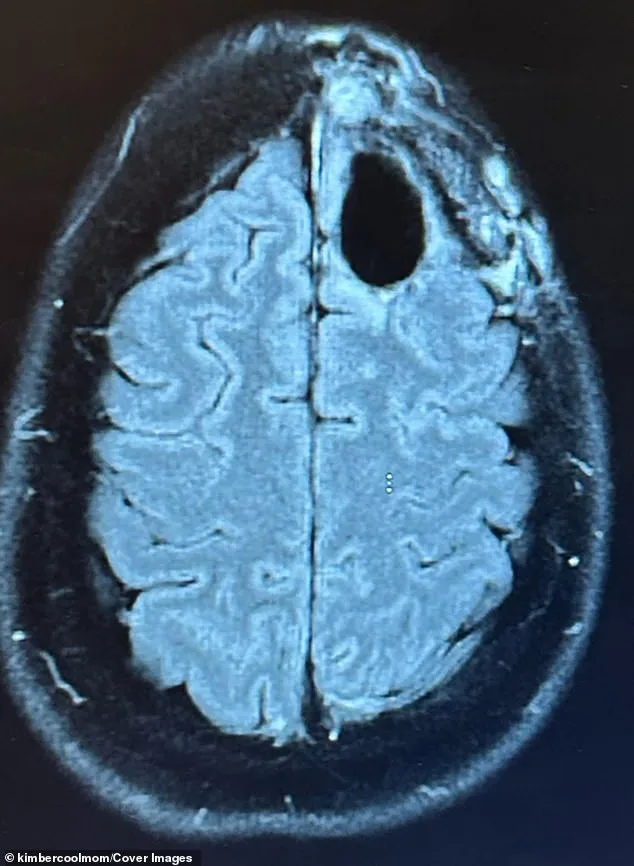

Kimberly Pelling's story is a harrowing blend of medical horror and personal resilience. Diagnosed with grade-four IDH-mutant anaplastic astrocytoma in August 2022, just four months after giving birth, she was told she had at most three years to live. The tumor, located in her frontal lobe, was aggressive and typically incurable. It began stealing her concentration, memory, and even parts of her personality. 'Nothing prepares you for that moment,' she said. 'It was devastating.'

Her journey began with night terrors that led to an MRI revealing a lime-sized tumor. The biopsy confirmed the worst: grade-four astrocytoma, a type of brain cancer with a median survival of around 31 months. But Pelling's story took a different turn. After her initial treatment failed, she pivoted to a carnivore diet, relying on grass-fed beef, eggs, and butter, while eliminating sugar. She also adopted a regimen of supplements, including methylene blue, curcumin, and melatonin, each chosen for their purported anti-cancer properties.

In 2025, a routine scan delivered news that defied her original prognosis: no evidence of cancer. 'I walked into that appointment prepared for anything,' she said. 'Hearing there was no evidence of cancer felt surreal.' Yet she remains cautious. 'The cancer might come back,' she acknowledges. 'But today, I'm too busy living to worry about dying.'